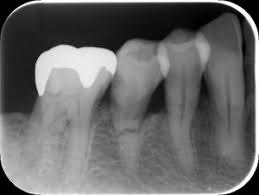

②、こんな感じで神経が出てきた場合

神経をとるか、保存するか。ドクターとその状況によります。